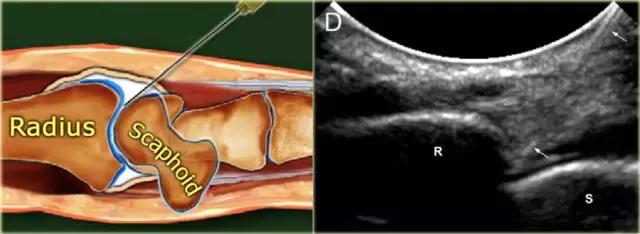

桡腕关节 患者仰卧,手腕靠在45°海绵或卷起的毛巾上。在一些情况下,将手腕保持在尺骨偏离中可能是有帮助的,以便更多地打开关节空间。

在超声波上识别桡骨和舟骨之间的空间。在超声引导下,将23-25号,30mm针推进到指向半径的关节表面的关节中,直到感觉到与桡骨接触。在确保针的尖端没有刺入软骨中,注射2-4mL对比度。针的斜面面向关节空间,并且看到对比度流入关节。